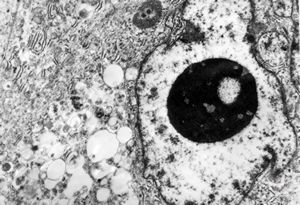

F,64y. | adenocarcinoma

F,64y. | adenocarcinoma